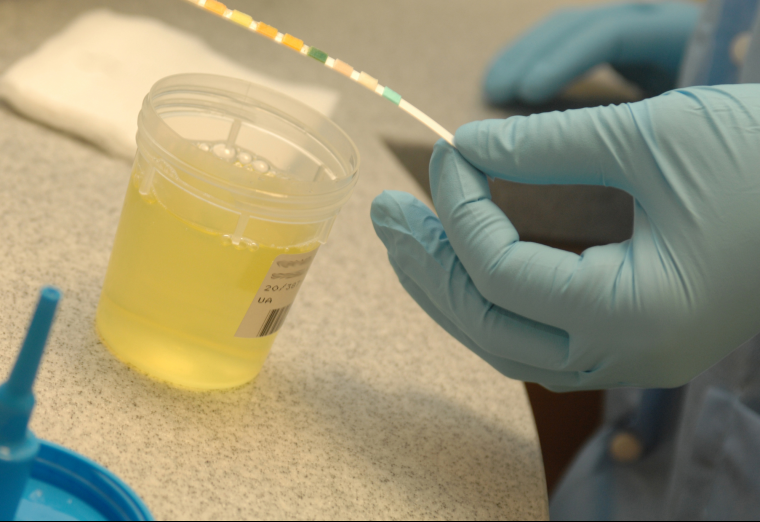

20. Your chances of developing a UTI increases

Image source/Top Doctors

A Urinary Tract Infection or UTI for short can be caused by holding pee in for too long. Bacteria can multiply as a result of not peeing which resultantly leads to an increase risk of UTIs. If you're a person with a history of frequent UTIs then you're at even more risk!Advertisement

25. Your pee will turn a funny colour

Image source/HubPages

If you find yourself for some unknown reason holding your pee in for too long, don't be shocked to find it having a rotten smell and a dark orange color. While you hold your pee in for too long, due to the bacteria build up, it will begin to turn a funny orangey color. Not to forgot it will stink your bathroom out!Advertisement